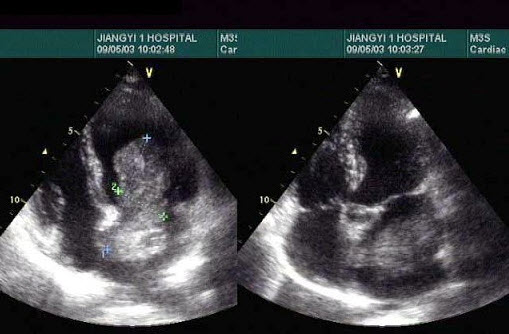

9、单项选择题

女,51岁,纳差、消瘦。结合超声声像图,诊断为()

如图,二维超声心动图中,此为____________切面。